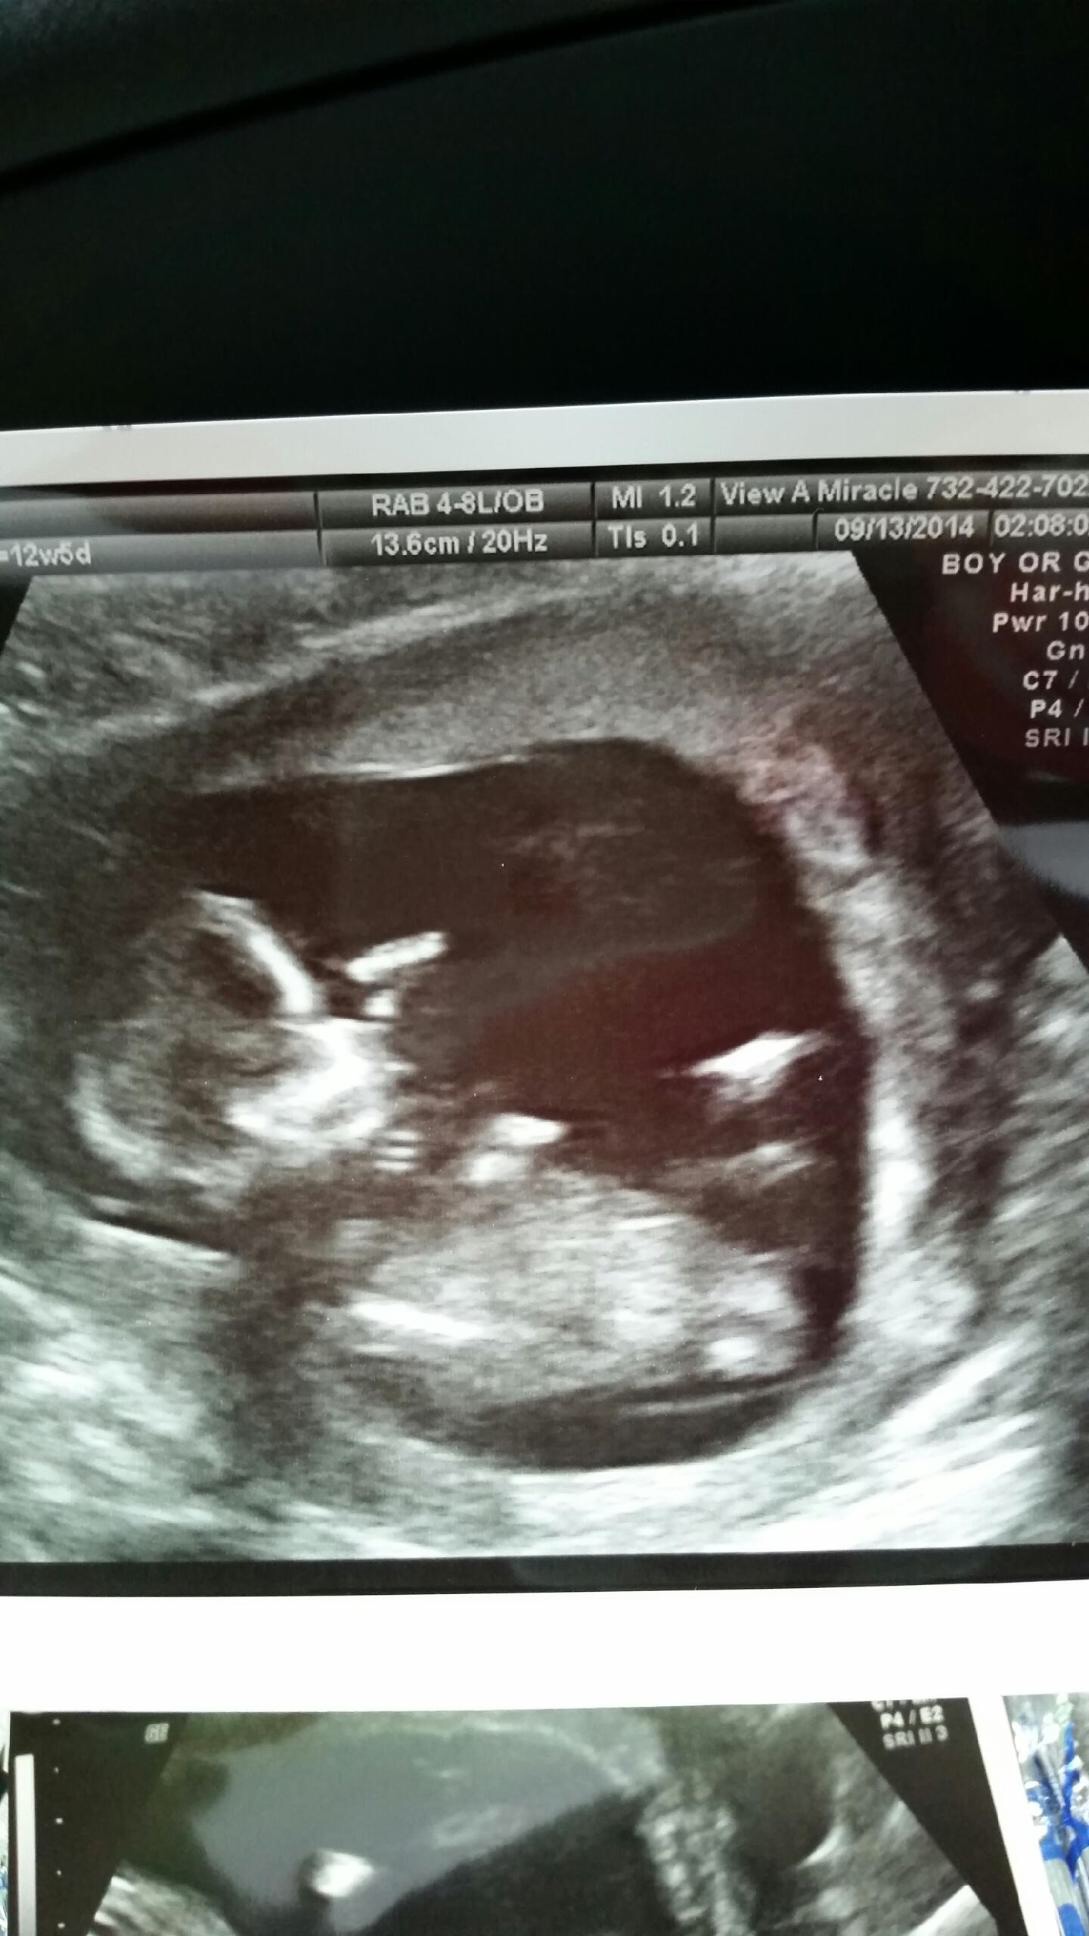

i got 2-3 more on a cd...

Attachment 20899

Hmmm. Honestly from these I'd say boy. It's still early though.